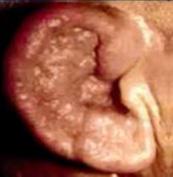

A la otoscopía el proceso inflamatorio es menor comparado con la otitis externa difusa, los crecimientos micóticos se verán como finos filamentos de hongos y esporas que se asemejan al moho que crece en los alimentos en mal estado. Las esporas de A. niger parecen un polvo fino de carbón rociado en el canal auditivo. El Aspergillus también puede parecerse a un periódico húmedo o papel secante. Las infecciones por cándida generalmente se asocian con un material blando, blanco, parecido a las sebáceas que puede llenar el canal auditivo en casos graves. Una pseudomembranosa a menudo recubre el canal auditivo que, cuando se retira, revela una membrana granular friable subyacente.